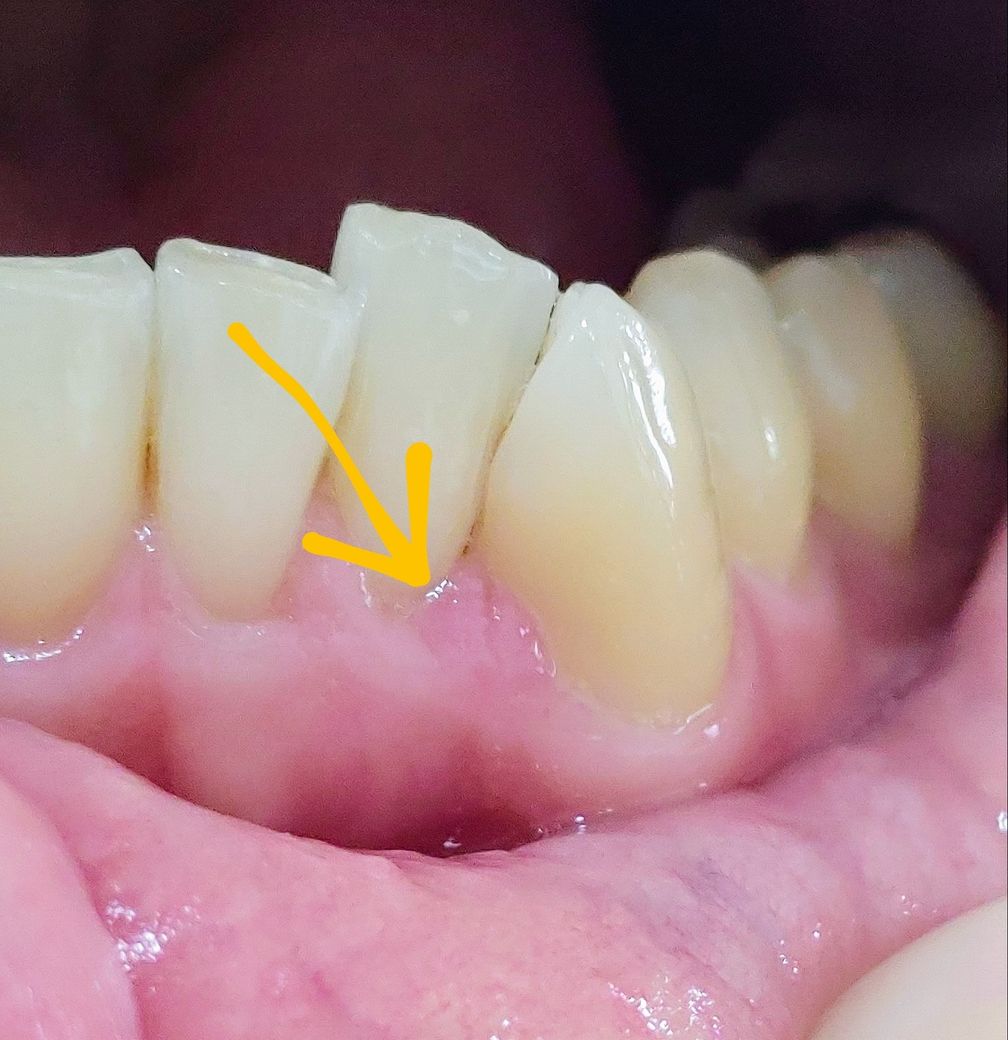

어금니 크라운 후 앞니 사이에 잇몸염증 갈라짐. 부음.

2주 후 부터 이빨을 꽉 물면 앞니 쪽에 통증이 약하게 있다가, 지금(1달)은 갈라짐과 부은듯 하게 통증이 생겼습니다.

어금니를 지었구나로 치료를 한 것과 송곳니 쪽에 잇몸이 접히는 현상은 서로 연관이 없습니다.

지르코니아로 치료를 했을 경우 교합의 변화가 생기면서 물리는 것이 다르게 물릴 수 있습니다 교합 간섭이 있는 경우에는 해당부의 교합 간섭을 조정해 주면 됩니다 송곳니의 잇몸은 대부분 시간이 지나면서 괜찮아지게 됩니다.

송곳니가 어긋나 있을 경우에는 송곳니 사이에 이물질이 들어갈 수 있기 때문에 치실로 관리를 해 주는 것이 좋습니다.

• 앞니 사이에 잇몸염증 갈라짐과 붓는 증상은 어금니에 크라운을 한 것과는 연관이 있지는 않습니다. 현재 앞니 부위에 불편감 및 염증이 있는 경우 치과에 다시 방문하여 진료를 받고 치료를 받길 권합니다.

1. 어금니 신경치료+크라운과는 별개의 문제로 봐야할 것 같습니다

2. 해당 부위 잇몸이 현재 약간 부종이 있어보입니다. 정확히 잇몸 관련 문제일지 아니면 주변 치아 문제일지는 치과에서 검사를 해봐야겠습니다.